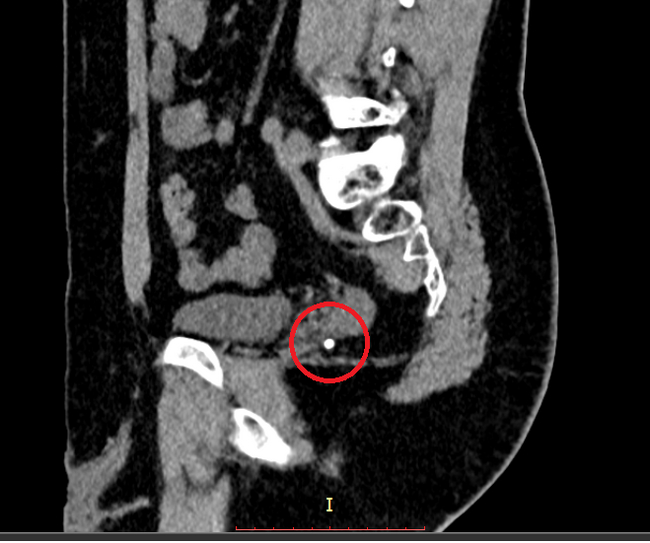

Мазок на инфекции, УЗИ, Сумамед "на всякий случай". Мазок - это тоже больно. Это такой ёршик, который тебе прямо туда засовывают. Но не так больно, как писать. Анализы хорошие, а вот УЗИ... Песочек у меня. Не камни - много мелкой фракции. Видимо что-то покрупнее проскочило наружу, оцарапало мочеточник, воспалилось и теперь болит.

Что делать? Пейте толокнянку по паре столовых ложек в качестве мочегонного. И ждите пока всё выйдет. Потом снова на УЗИ. И я пью. Неделю пью. Две пью. Болит уже не только член. Больно теперь еще и внутри. Иду снова к доктору. Снова УЗИ.

- Всё нормально, - говорит, - песочек пошёл, - говорит, - лоханка расширена и болит. Пейте толокнянку. И брусничный лист. По две столовых ложки. Перестанет болеть - приходите.